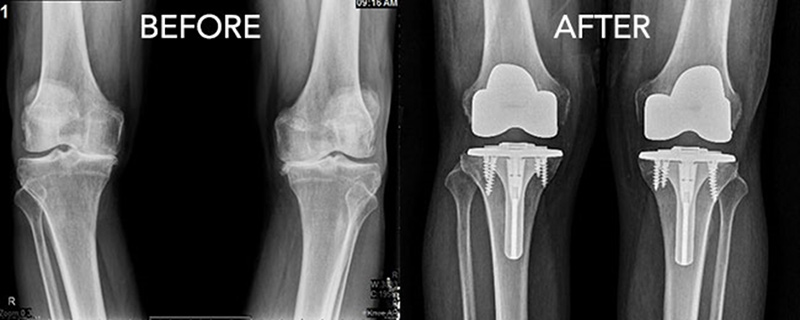

제 3 정형외과전문진료분야 슬관절, 고관절, 견관절, 관절경, 인공관절, 골다공증

-대한슬관절학회 정회원